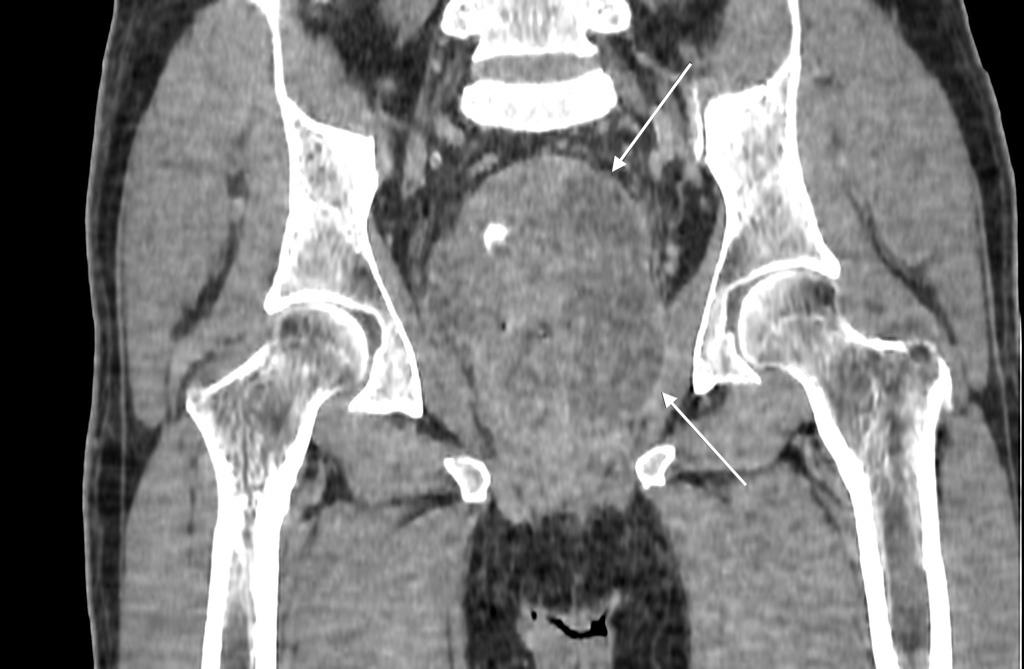

КТ-исследование абсцесса малого таза: Визуализация и диагностика

Раздел: Фотоальбом решений